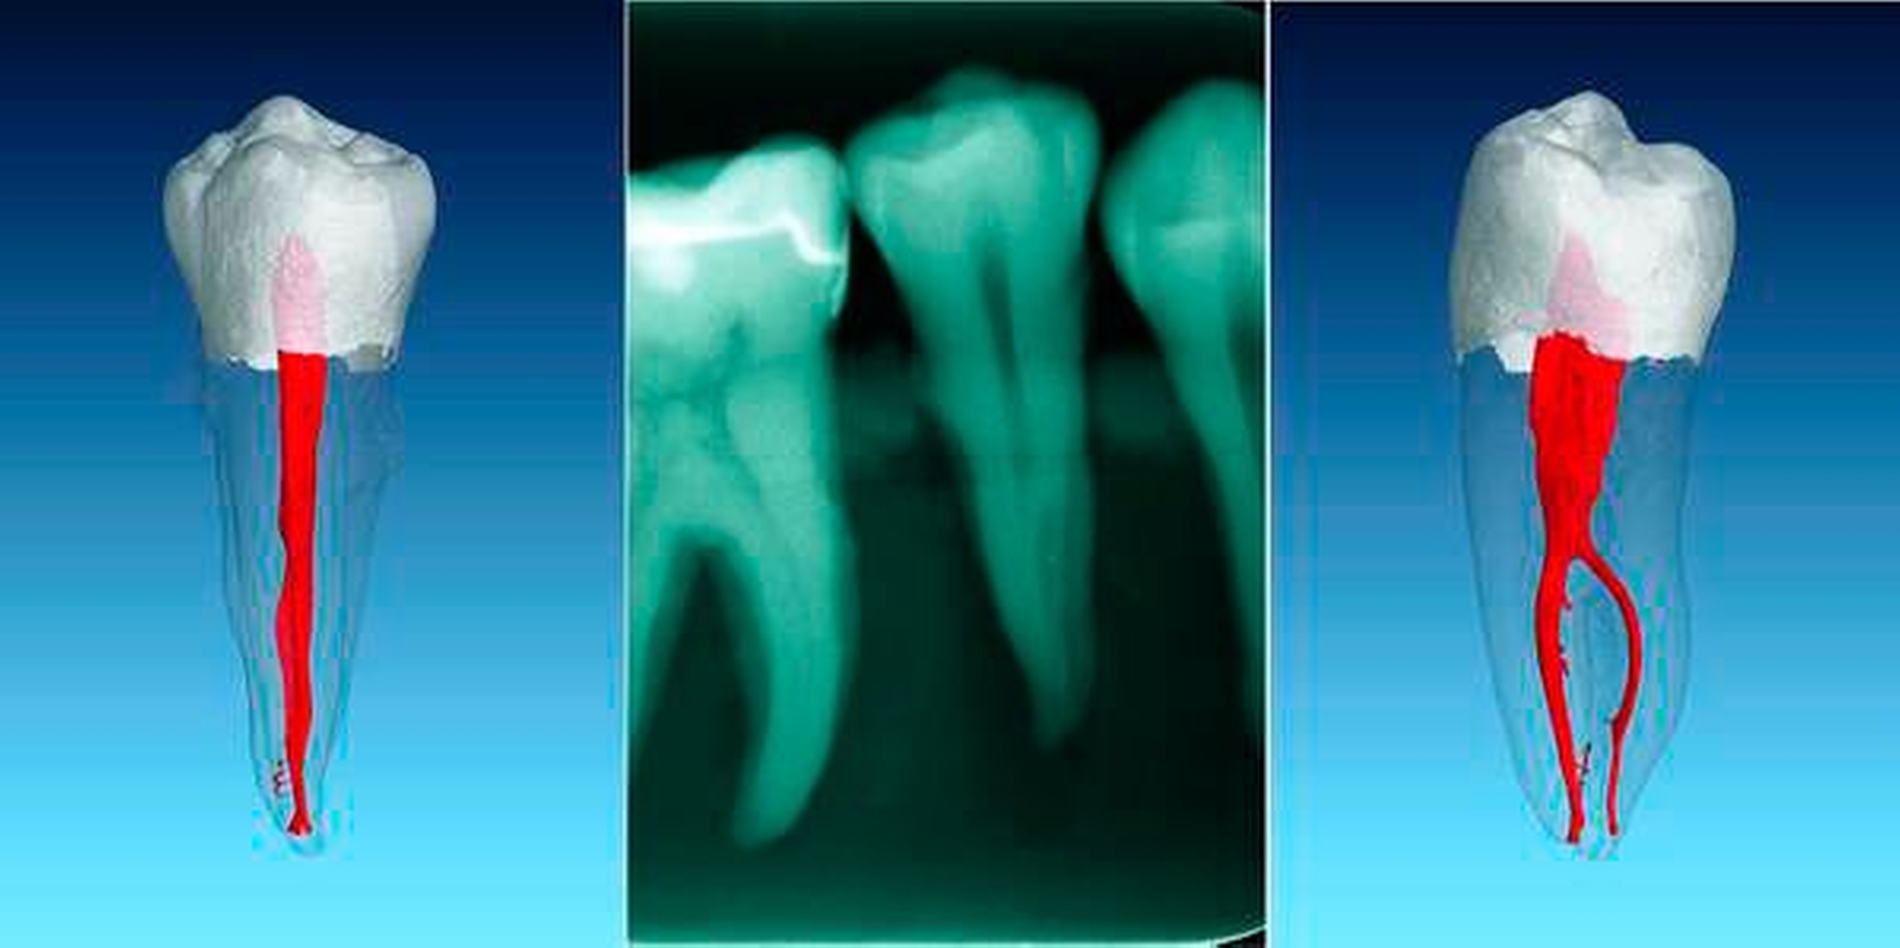

In einer Übersichtsarbeit, die acht Studien über die Anatomie von ersten Unterkiefer-Prämolaren zusammenfasst, ergab sich eine Prävalenz von mehr als einem Kanal in 24,2 Prozent aller Fälle [Cleghorn et al., 2007a]. Dabei überwiegen die zweikanaligen Prämolaren, die Prävalenz von drei Kanälen liegt bei unter 1 Prozent [Bürklein et al., 2017] (Abbildungen 4 und 5). Bei den zweikanaligen Zähnen zeigt sich üblicherweise ein weitlumiger Kanal von koronal nach apikal, von dem im mittleren oder im apikalen Drittel ein kleinerer lingualer Anteil abzweigt. Dieses Phänomen kann sehr ausgeprägt sein und macht die Behandlung extrem schwer (Abbildung 6).

Durch ein genaues Betrachten der präendodontischen, apikalen Röntgenaufnahme können verschiedene Hinweise für das Vorliegen mehrerer Kanäle erkannt werden. Verschwindet ein im Röntgenbild koronal gut sichtbarer Wurzelkanal scheinbar im Verlauf zum Apex oder verengt er sich sehr deutlich, ist das sehr häufig ein Hinweis auf eine Kanalaufzweigung in Strahlenrichtung [England et al., 1991] (Abbildung 9). Weitere Hinweise sind laut Hülsmann [Hülsmann, 2001]: